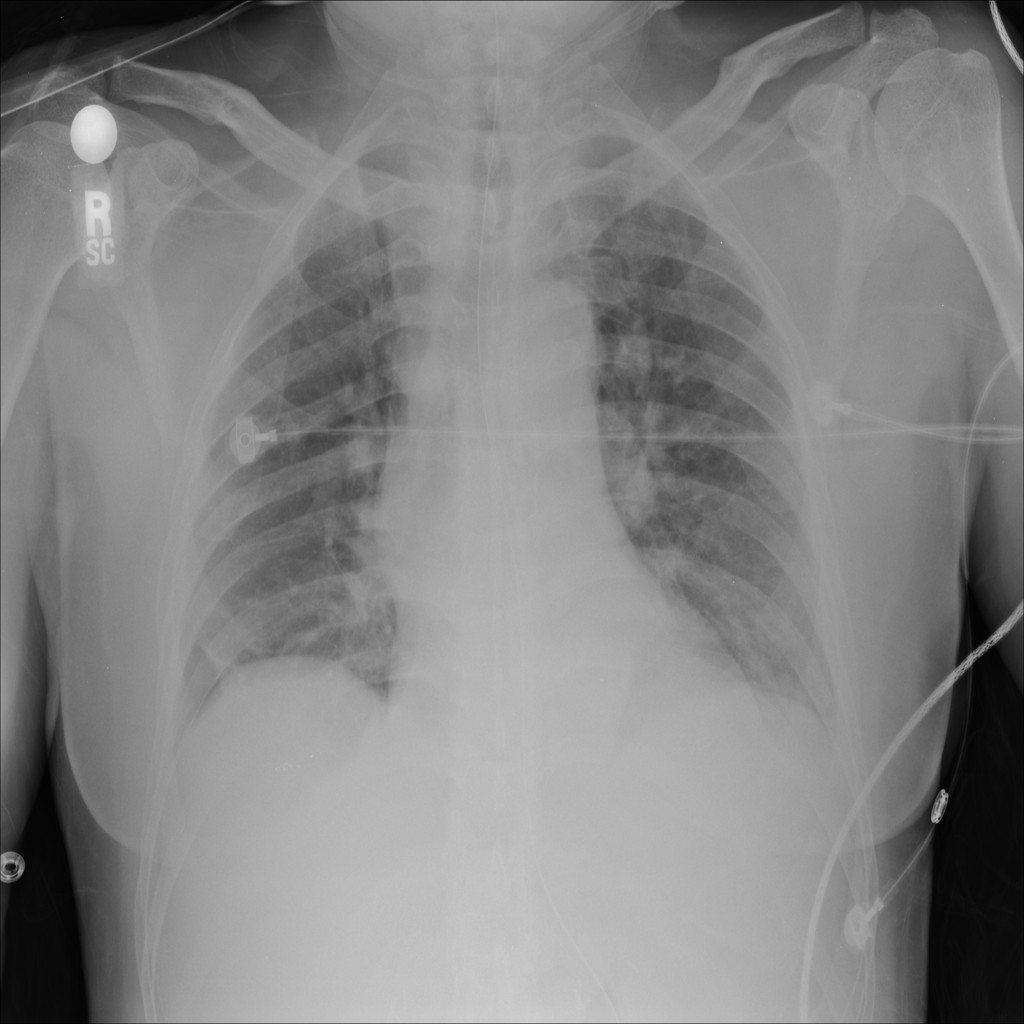

Showing up to 90 reference images for Nodule.

PAT-FB8F · IMG-000Nodule

PAT-FB8F · IMG-000

PA